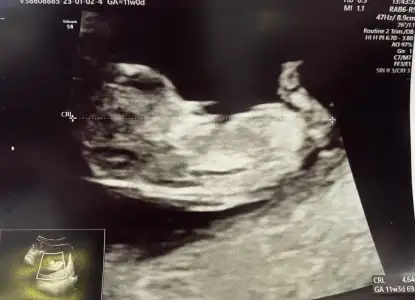

11 Haftalık olduk bizde kızlar tahminlerde değişen var mı bakabilir misiniz 🙋🏻‍♀️

Eklentiler

• IMG_5273.webp

IMG_5273.webp

35,9 KB · Görüntüleme: 61

• IMG_5272.webp

IMG_5272.webp

44,5 KB · Görüntüleme: 49

• IMG_5271.webp

IMG_5271.webp

45,8 KB · Görüntüleme: 72